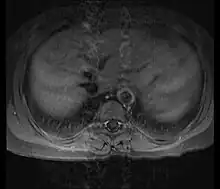

Axial T1-weighted post-gadolinium MRI in a patient with Takayasu arteritis showing thickened, enhancing aortic wall, consistent with large vessel vasculitis

Although the cause of Takayasu arteritis is unknown, the condition is characterized by segmental and patchy granulomatous inflammation of the aorta and its major derivative branches. This inflammation leads to arterial stenosis, thrombosis, and aneurysms.[3] There is irregular fibrosis of the blood vessels due to chronic vasculitis, leading to sometimes massive intimal fibrosis (fibrosis of the inner section of the blood vessels).[5] Prominent narrowing due to inflammation, granuloma, and fibrosis is often seen in arterial studies such as magnetic resonance angiography (MRA), computed tomography angiography (CTA), or arterial angiography (DSA).